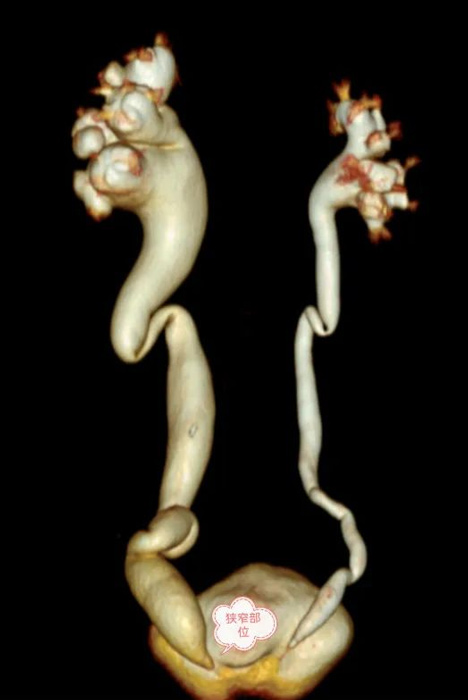

近期,53歲的王女士突發(fā)右側腰腹痛,通過朋友介紹,慕名找到我院泌尿外科找付東方主任問診,付主任在為王女士診查后,發(fā)現王女士疼痛的原因是她的右側輸尿管末端有結石,但是,檢查顯示王女士的左側輸尿管問題更嚴重:

左側輸尿管全程擴張

左腎重度積水

左側輸尿管膀胱連接處狹窄

在經過付主任和鄭州市中心醫(yī)院常駐專家唐曉龍主任仔細閱片和研究手術方案后,決定行完全微創(chuàng)手術治療該疾病,即腹腔鏡下左側輸尿管膀胱再植術。

手術難點:需先行離斷迂曲變形的輸尿管,再把輸尿管裁剪后重新種植的膀胱上,

關鍵點:輸尿管膀胱的再吻合。